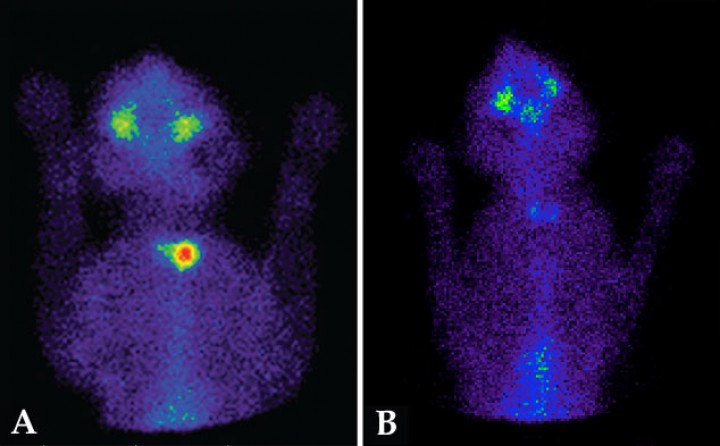

- Para calcular las dosis de radiofármaco (dosis personalizadas) en el tratamiento con yodo radiactivo (131I). El objetivo del tratamiento con 131I en gatos hipertiroideos es la destrucción de todo tejido hiperfuncional respetando el tejido tiroideo sano. La gammagrafía nos aporta datos del volumen y del porcentaje de captación de tecnecio[ Peterson ME, Guterl JN, Rishniw M, Broome MR. Evaluation of quantitative thyroid scintigraphy for diagnosis and staging of disease severity in cats with hyperthyroidism: comparison of the percent thyroidal uptake of pertechnetate to thyroid-to-salivary ratio and thyroid-to-background ratios. Vet Radiol Ultrasound. 2016; 57(4):427-440. [PubMed] ] del tejido hiperfuncional, lo cual nos permite ajustar las dosis en cada caso para obtener un mayor porcentaje de curación, minimizando el riesgo de producir hipotiroidismo iatrogénico (Fig. 5).[ Xifra MP, Peterson ME. Hipertiroidismo felino. En: Pérez MD, Arenas C, Melian C (eds): Manual de Endocrinología en Pequeños Animales. 2ª ed. Barcelona, España. Multimédica; 2018:143-192. , Peterson ME, Xifra MP, Broome MR. Treatment of hyperthyroidism: radioiodine. En: Feldman EC, Fracassi F, Peterson ME (eds). Feline Endocrinology. Milan, Italia: Edra; 2019:227-254. , Xifra Rubio P, Serrano Garcia, SI, Peterson ME. Hipertiroidismo felino: Diagnóstico y evolución de la enfermedad mediante gammagrafía y tratamiento con yodo radiactivo (131I). Rev Cient Esp Med Intern Peq Anim 2018;2:25-31. , Lucy JM, Peterson ME, Randolph JF et al. Efficacy of low-dose (2 mCi) versus standard-dose (4 mCi) radioiodine treatment for cats with mild-to-moderate hyperthyroidism. J Vet Intern Med. 2017; 31:326-334. [PubMed] , Peterson ME, Guterl JN, Nichols R, Rishniw M. Evaluation of serum thyroid-stimulating hormone concentration as a diagnostic test for hyperthyroidism in cats. J Vet Intern Med. 2015; 29:1327-1334. [PubMed] ]

<p>Gammagrafías tiroideas, pretratamiento y postratamiento con <sup>131</sup>I, de un gato hipertiroideo. (<strong>A</strong>) Gammagrafía pretratamiento que muestra un patrón unilateral derecho con aumento de captación de <sup>99m</sup>Tc-pertecnetato (ratio T/S: 4,5). El paciente fue tratado con una dosis baja de <sup>131</sup>I (1,4 mCi), ajustada en base a los datos obtenidos en la gammagrafía previa. (<strong>B</strong>) Gammagrafía a los 6 meses postratamiento, que muestra el restablecimiento del eutiroidismo sin producir hipotiroidismo iatrogénico (ratio T/S: 1,2).</p>

Gammagrafías tiroideas, pretratamiento y postratamiento con 131I, de un gato hipertiroideo. (A) Gammagrafía pretratamiento que muestra un patrón unilateral derecho con aumento de captación de 99mTc-pertecnetato (ratio T/S: 4,5). El paciente fue tratado con una dosis baja de 131I (1,4 mCi), ajustada en base a los datos obtenidos en la gammagrafía previa. (B) Gammagrafía a los 6 meses postratamiento, que muestra el restablecimiento del eutiroidismo sin producir hipotiroidismo iatrogénico (ratio T/S: 1,2).

- Para valorar la evolución en gatos hipertiroideos tratados con cirugía o yodo radiactivo. La realización de gammagrafías tiroideas postratamiento nos permite confirmar el éxito de los tratamientos realizados (eliminación de la totalidad del tejido hiperfuncional y existencia de tejido remanente sano).[ Xifra MP, Peterson ME. Hipertiroidismo felino. En: Pérez MD, Arenas C, Melian C (eds): Manual de Endocrinología en Pequeños Animales. 2ª ed. Barcelona, España. Multimédica; 2018:143-192. , Peterson ME, Xifra MP, Broome MR. Treatment of hyperthyroidism: radioiodine. En: Feldman EC, Fracassi F, Peterson ME (eds). Feline Endocrinology. Milan, Italia: Edra; 2019:227-254. , Xifra Rubio P, Serrano Garcia, SI, Peterson ME. Hipertiroidismo felino: Diagnóstico y evolución de la enfermedad mediante gammagrafía y tratamiento con yodo radiactivo (131I). Rev Cient Esp Med Intern Peq Anim 2018;2:25-31. ]